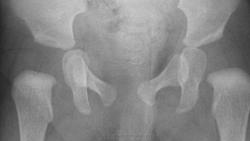

Да мне и расчерчивать не надо, я и так вижу, что подвывиха нет. Укладка достаточно асимметричная, толку то расчерчивать. Но и без расчерчивания видно, что линии Омбердана проходят через среднюю треть метафизов бедер, расстояния между шеечной шпорой и седалищной костью в норме (слева даже чуть меньше, чем справа). Да, не визуализируются еще ядра окостенения головок, возможно, есть замедление их оссификации, но с обеих сторон; может, есть небольшая скошенность крыши слева (надо померить угол). Я не исключаю небольшую дисплазию, но подвывиха нет.

Расчерчиваем. Делаем поправку на асимметричную укладку (зеленым цветом). Не обращаем внимания на линию Шентона (читаем у Садофьевой). Не обращаем внимание на отсутствие ядер окостенения (читаем там же). В итоге: подвывиха не видим. При наличии сильного желания, можно увидеть легкую дисплазию слева. Которая в ортопедическом лечении не нуждается, в оличие от подвывиха (жесткий ортопедический режим, отводящие приспособления, операция).

Да, когда еще нет головок, ось шейки провести сложно, поэтому предлагают проводить перпендикуляр к замыкательной пластинки метафиза. И вот он должен проецироваться на медиальную четверть ацетабули у детей до 6 мес в норме (а у старших детей ось шейки должна проецироваться на Y - образный хрящ). Но я никогда не видела, чтоб этот перпендикуляр проецировался на медиальную четверть, всегда на середину. Поэтому, если все остальные показатели в норме, я это во внимание не беру, но в тексте могу написать, иногда пишу децентрация головки, если еще что-то не так.

Слева увеличен угол скоса впадины, бедро смещено кверху и кнаружи на 2-3 мм.